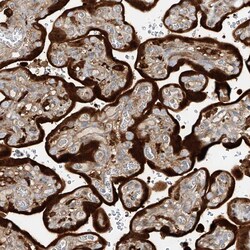

Invitrogen™ KYNU Polyclonal Antibody

Brand: Invitrogen™ PA583205

| Immunohistochemistry (Paraffin), Western Blot, Immunocytochemistry | |